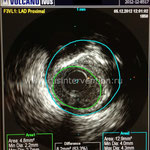

Осуществляется комплексная, структурная и функциональная сравнительная оценка исследуемых сегментов коронарных артерий. Оценка изображений, полученных с помощью ВСУЗИ, включает качественный структурный и количественный анализ состояния просвета и стенки коронарной артерии в месте стеноза и в прилегающих сегментах до эндоваскулярного вмешательства и на различных этапах операции ангиопластики и стентирования. Исследуется участок артерии на протяжении: не менее чем на 10 мм дистальнее зоны интереса и включая весь начальный сегмент и устье коронарной артерии.

Для получения объективных данных о просвете сосуда и количественных параметров используют количественную оценку:

• Площадь просвета — определяется путем очерчивания курсором внутренней поверхности сосуда по окружности (измеряется в мм2).

• Общая площадь сосуда — определяется путем очерчивания курсором наружной поверхности сосуда по окружности (измеряется в мм2).

• Процент стеноза по площади – расчетный показатель, определяется по формуле (общая площадь сосуда – площадь просвета)/общая площадь сосуда х 100.